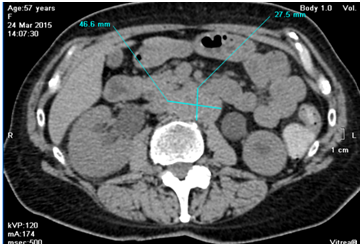

March 2015 she was admitted to urology clinic with her serum creatinine raised up to 450µmol/L, CT confirmed bilateral ureterohydronephrosis, and found right kidney enlargement and retroperitoneal mass with bilateral ureteral compression (Figure 1). She was diagnosed with retroperitoneal fibrosis, underwent right kidney percutaneous nephrostomy and left ureteral stenting, her creatinine lowered to 241µmol/L and she was referred to our clinic for further evaluation.